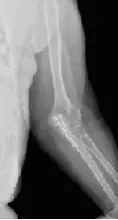

Інформативність обстеження: На рентгенограмах визначаються дистальний відділ плечової кістки і проксимальні відділи кісток передпліччя, ліктьовий і вінцевий відростки ліктьової кістки, головка і шийка променевої кістки, ліктьового відростка і заднього відділу суглобової поверхні блоку плечової кістки, ліктьовий відросток ліктьової кістки, медіальний і латеральний надвиростки плечовий кістки, головка променевої кістки, рентгенівська суглобова щілина плечелоктевом суглоба.

Лікар за рентгенівським знімком може швидко визначити тип перелому після травми, наприклад після сильного удару, падіння на лікоть, сильного викручування або загину руки. У цьому випадку на картині рентгену ліктьового суглоба можуть бути виявлені різні пошкодження кісток, перелом плеча, перелом відростків ліктьової кістки, перелом Монтеджі (перелом ліктьової кістки в області ліктьового суглоба з одночасним вивихом променевої кістки) та інші.